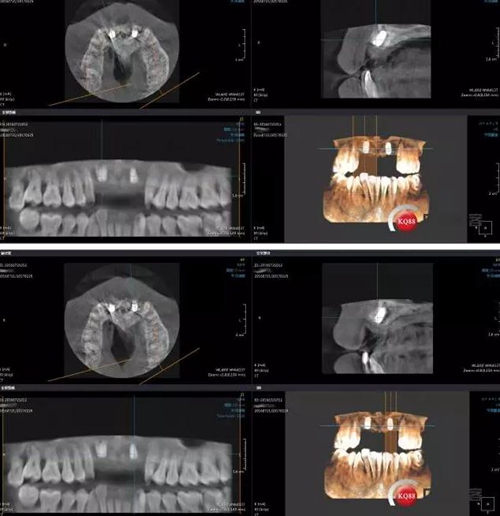

術(shù)前左上2 CBCT

術(shù)前右上2 CBCT

GBR術(shù)后CBCT

接下來是GBR五個月后CBCT,當(dāng)然(1-5月)中間也有拍全景,不一一展示了。

成骨效果尚可,進(jìn)行手術(shù)